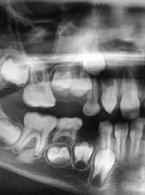

Inwazyjna resorpcja przyszyjkowa zęba 37

Zobacz więcej

lek. stom. Jacek Bilbin